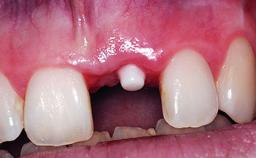

Replacement of a Compromised Upper Right Central Incisor: Hard- and Soft-tissue Augmentation, Late Placement of an RC Bone Level Implant

Bone Augmentation Horizontal|Simultaneous|Staged

Placement Protocol Early or late implant placement